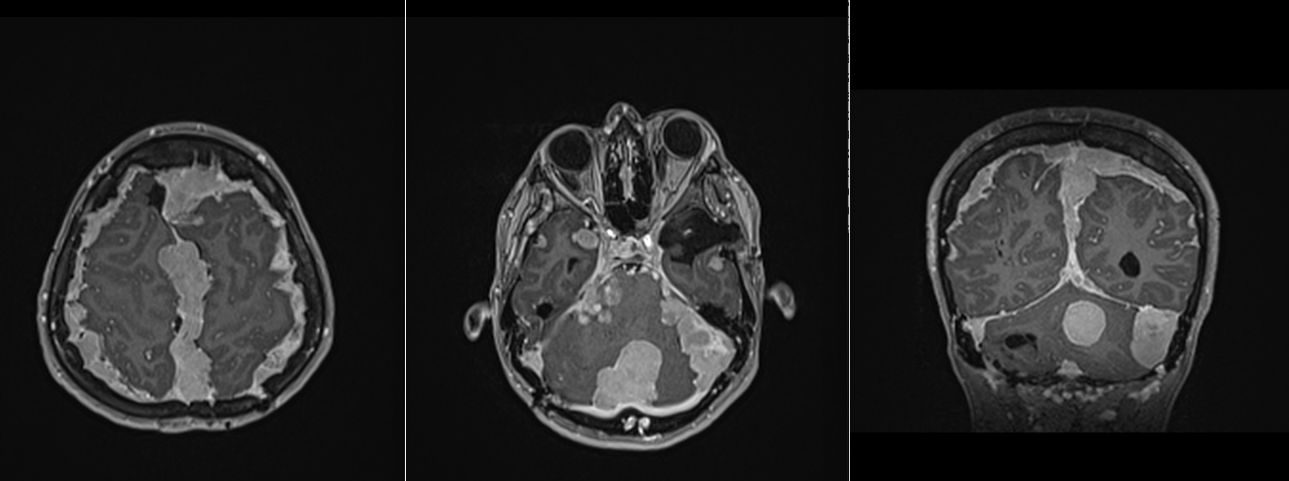

Meningioame multiple

Unii pacienți pot avea mai multe meningioame, cel mai adesea în contextul neurofibromatozei de tip 1 sau 2. La acești pacineți există o predispoziție a meningelui de a forma meningioame – așa numita meningiomatoză, ceea ce determină o evoluție nefavorabilă cu recidive rapide agravare progresivă.

- RMN – cea mai completă investigație, oferă detalii despre relația cu țesutul cerebral, vasele de sânge și nervii Captarea substanței de contrast este deosebit de importantă.